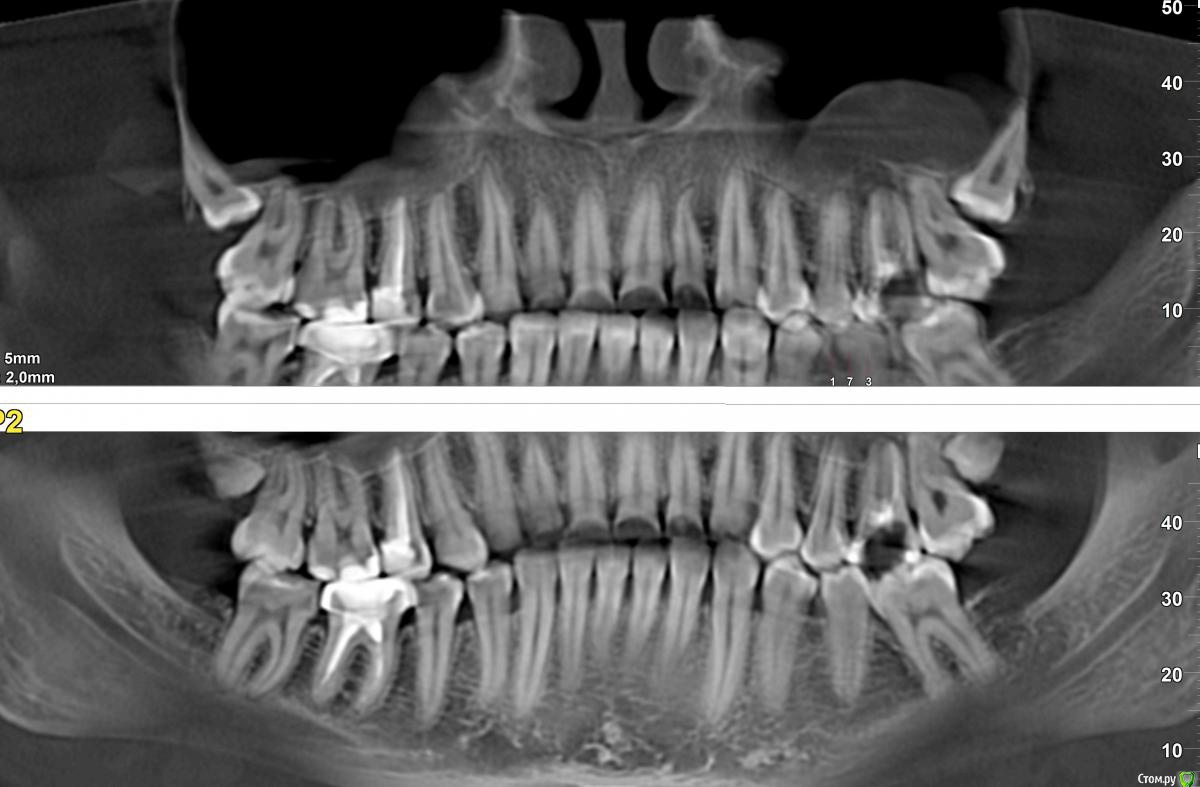

AndyAndy Опубликовано 6 октября, 2016 Поделиться Опубликовано 6 октября, 2016 Ах, как 18-ый зуб красиво лежит.... Ссылка на комментарий

korsa Опубликовано 13 октября, 2016 Автор Поделиться Опубликовано 13 октября, 2016 (изменено) Ах, как 18-ый зуб красиво лежит.... Красиво, в каком понимании? они, 8ки, так уже давно, не беспокоят и подскажите, пожалуйста, что за потемнения под корнями нижнего зуба, последний, рядом с коронкой? он пока тоже не дает о себе знать. Изменено 13 октября, 2016 пользователем korsa Ссылка на комментарий

korsa Опубликовано 13 октября, 2016 Автор Поделиться Опубликовано 13 октября, 2016 вот полный снимок Ссылка на комментарий

DmitrySH Опубликовано 13 октября, 2016 Поделиться Опубликовано 13 октября, 2016 Скорее всего ничего страшного и лечение не требуется. Надо сделать тест на витальность зуба 47. Ссылка на комментарий